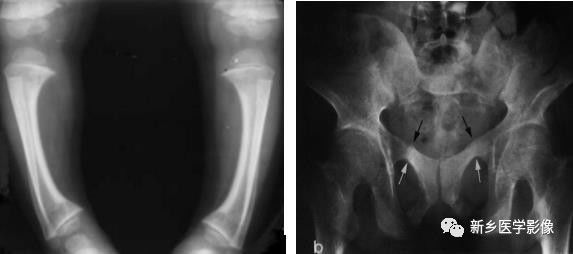

骨质软化X线图像

a.小腿X线正位片显示两侧胫骨变形,形成“O”形腿

b.骨盆正位片示骨密度减低、骨皮质变薄和骨小梁减少变细且边缘模糊。耻骨上支见假骨折线(↑)。